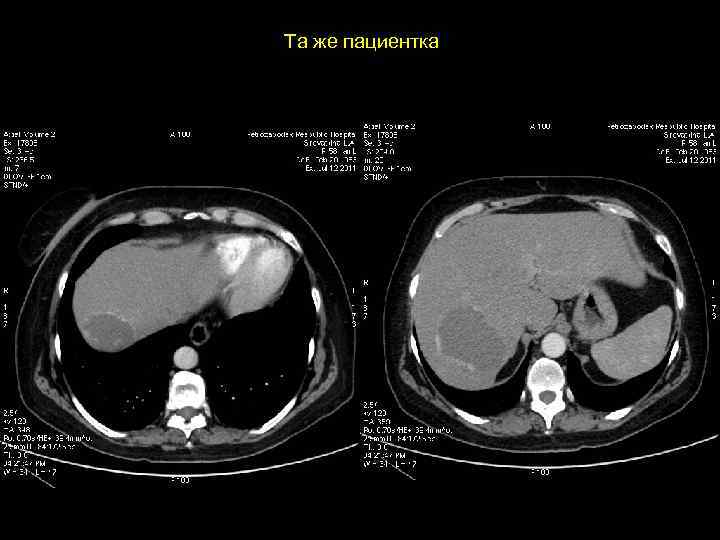

АКТУАЛЬНЫЕ ВОПРОСЫ РЕНТГЕНОЛОГИИ ЛУЧЕВАЯ ДИАГНОСТИКА ОЧАГОВЫХ ПОРАЖЕНИЙ ПЕЧЕНИ ФОКУСНАЯ (УЗЛОВАЯ) ГИПЕРПЛАЗИЯ ПЕЧЕНИ Ультразвуковая семиотика: - образование небольших размеров - без капсулы - слегка гипоэхогенно (мало чем отличается от неизмененной паренхимы)

АКТУАЛЬНЫЕ ВОПРОСЫ РЕНТГЕНОЛОГИИ ЛУЧЕВАЯ ДИАГНОСТИКА ОЧАГОВЫХ ПОРАЖЕНИЙ ПЕЧЕНИ ФОКУСНАЯ (УЗЛОВАЯ) ГИПЕРПЛАЗИЯ ПЕЧЕНИ Компьютерно-томографическая семиотика: - низкоплотностное образование ( до 30 ед Н ) - без капсулы - при болюсном введении РКВ очень быстро накапливают (в течении 1 -2’) и очень быстро выводят РКВ, вновь становясь низкоплотностными образованиями

Клиническое наблюдение. Пациентка К, 1966 г. р.

Та же пациентка